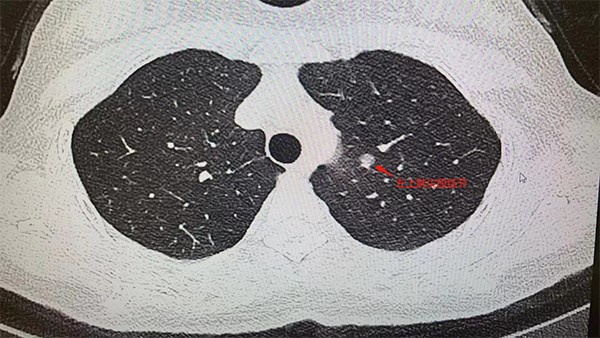

患者胸部CT檢查圖片。重慶西區醫院供圖

姚珂介紹,結合影像學特征,王女士的肺小結節,惡性征象明顯。制定手術方案時,姚珂考慮到該患者病灶靠近主支氣管,位置較深,需要游離的血管較多,為保證精準切除病灶且最大程度保護患者肺功能,通過穿刺定位+CT三維重建引導,行單孔胸腔鏡下肺聯合亞段切術,最為合適。目前,手術取得成功。